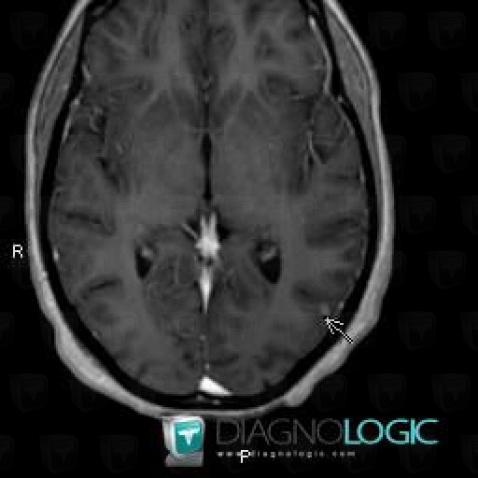

Voici les informations spécifiques à l'image clé ci dessus:

- Diagnostic Tuberculose , Localisation(s) Parenchyme pulmonaire, comportant les gammes Condensation alvéolaire localisée, Condensation alvéolaire aigüe

Voici les informations spécifiques à l'image clé ci dessus:

- Diagnostic Tuberculose (lié à Abcès), Localisation(s) Hémisphères cérébraux, comportant les gammes Lésion intracérébrale à réhaussement modéré

Voici les informations spécifiques à l'image clé ci dessus:

- Diagnostic Tuberculose (lié à Abcès), Localisation(s) Hémisphères cérébraux, comportant les gammes Lésion intracérébrale à réhaussement modéré